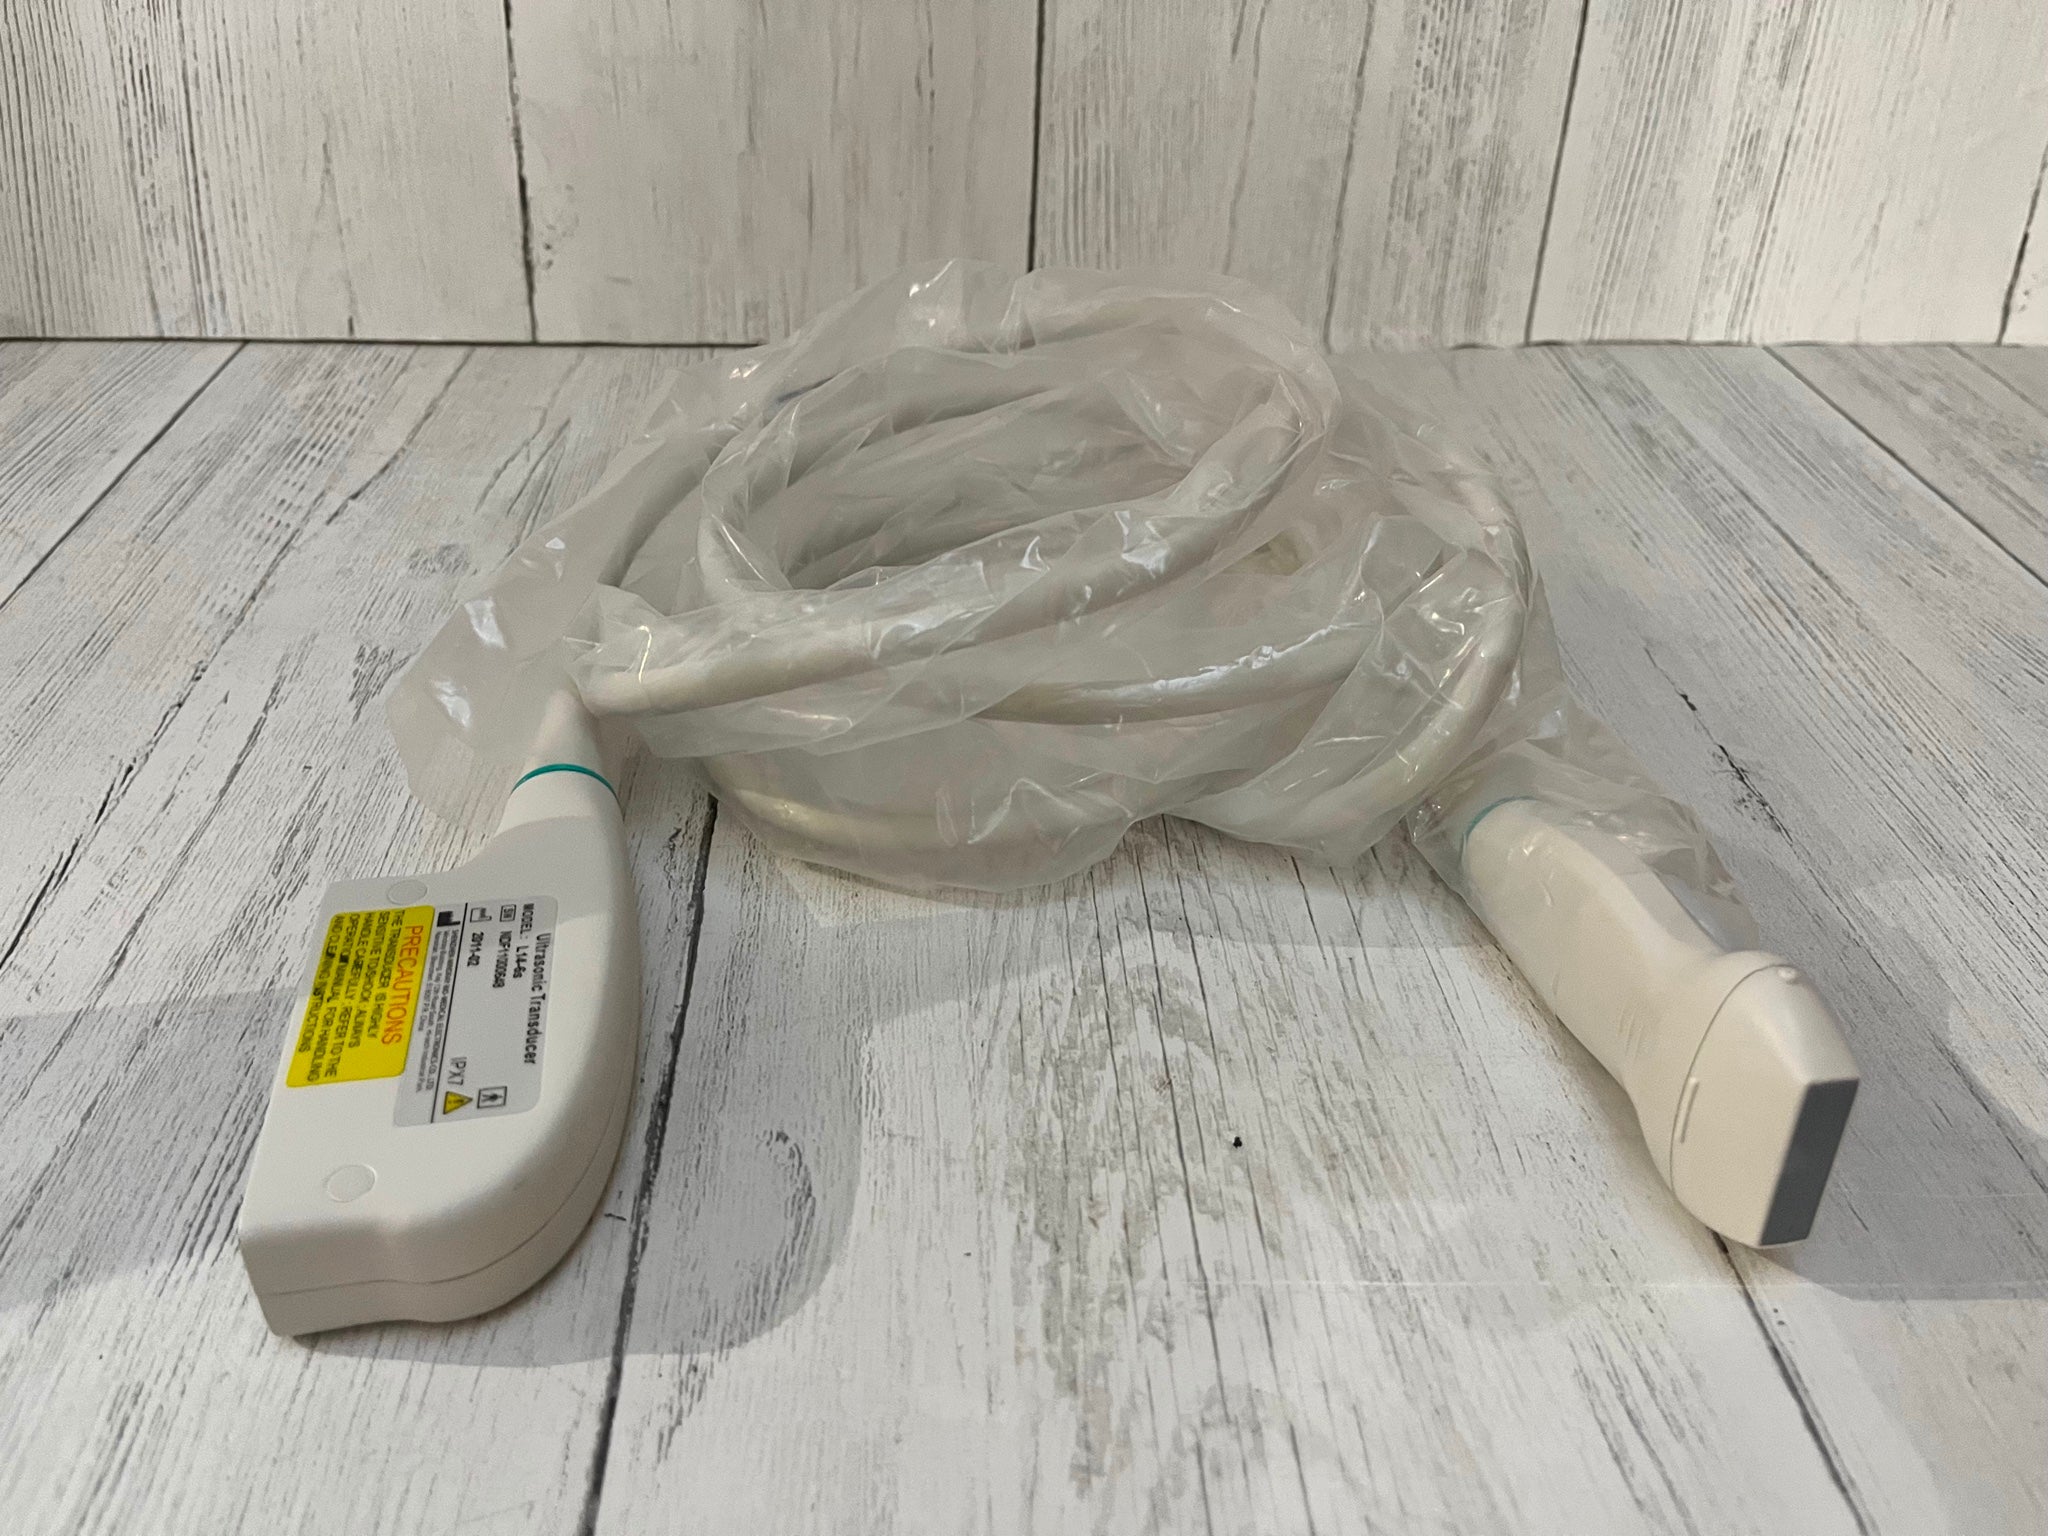

DIAGNOSTIC ULTRASOUND MACHINES FOR SALE

Sonosite M-Turbo Portable Ultrasound Machine

Sale price$ 9,840.00